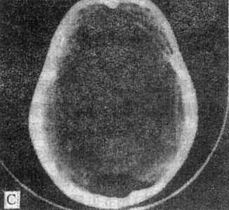

鞍上池的前方为两侧额叶后缘,后方可见中脑大脑脚,两侧毗邻颞叶海马沟回。

鞍上池内有视交叉、视束、垂体柄、颈内动脉、基底动脉等。

六角形鞍上池由交叉池和脚间池组成。

前角伸向两侧额叶之间,并延续为大脑纵裂池;前外侧角伸向额叶与颞叶之间,延续为大脑外侧窝池;后外侧角伸向大脑与中脑之间,延续为环池;后角是脚间池。